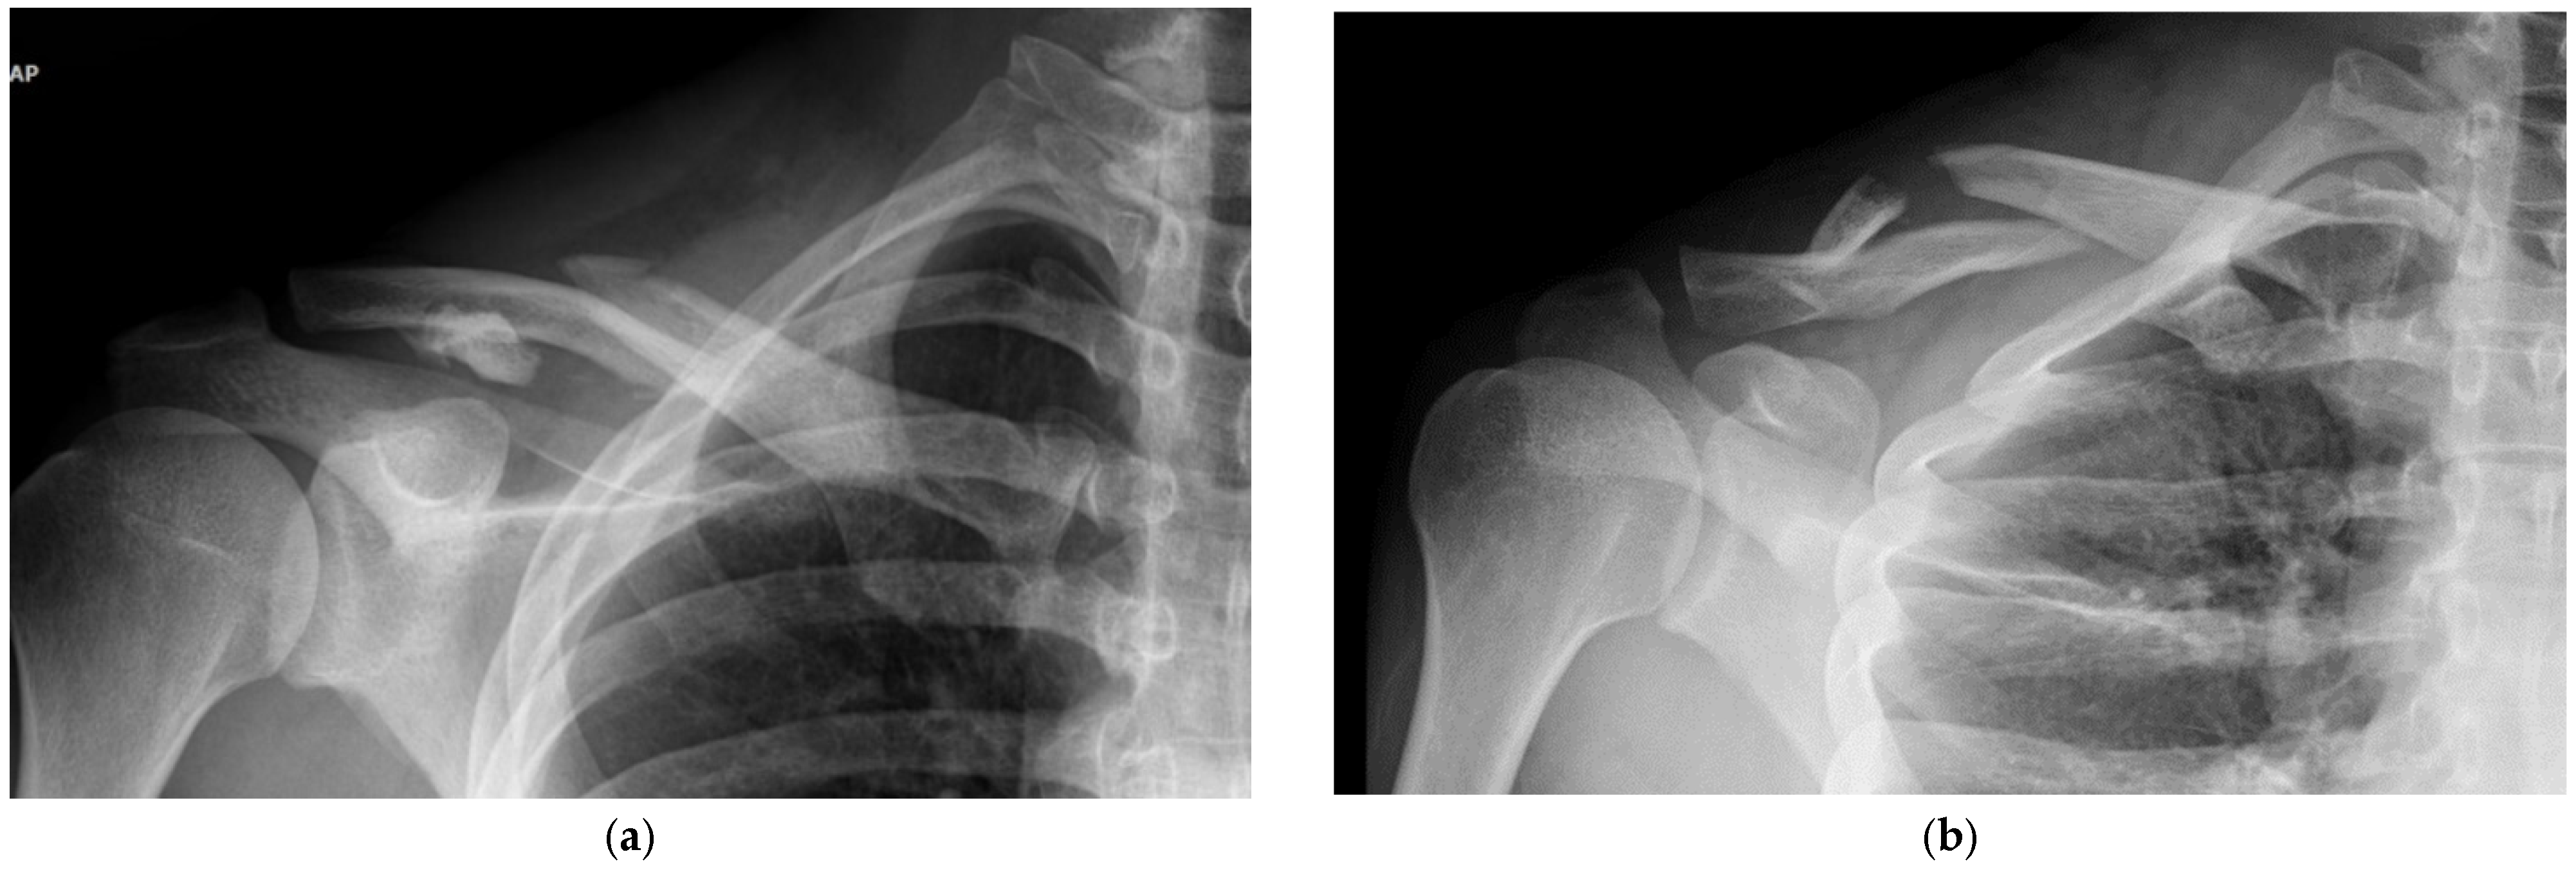

Intuitive and Minimally Invasive Surgical Technique for Comminuted Mid-Shaft Clavicle Fractures: Fixation with an Anterior Mini Plate and Superior Locking Compression Plate

2.1. Clinical Series

2.2. Surgical Protocol